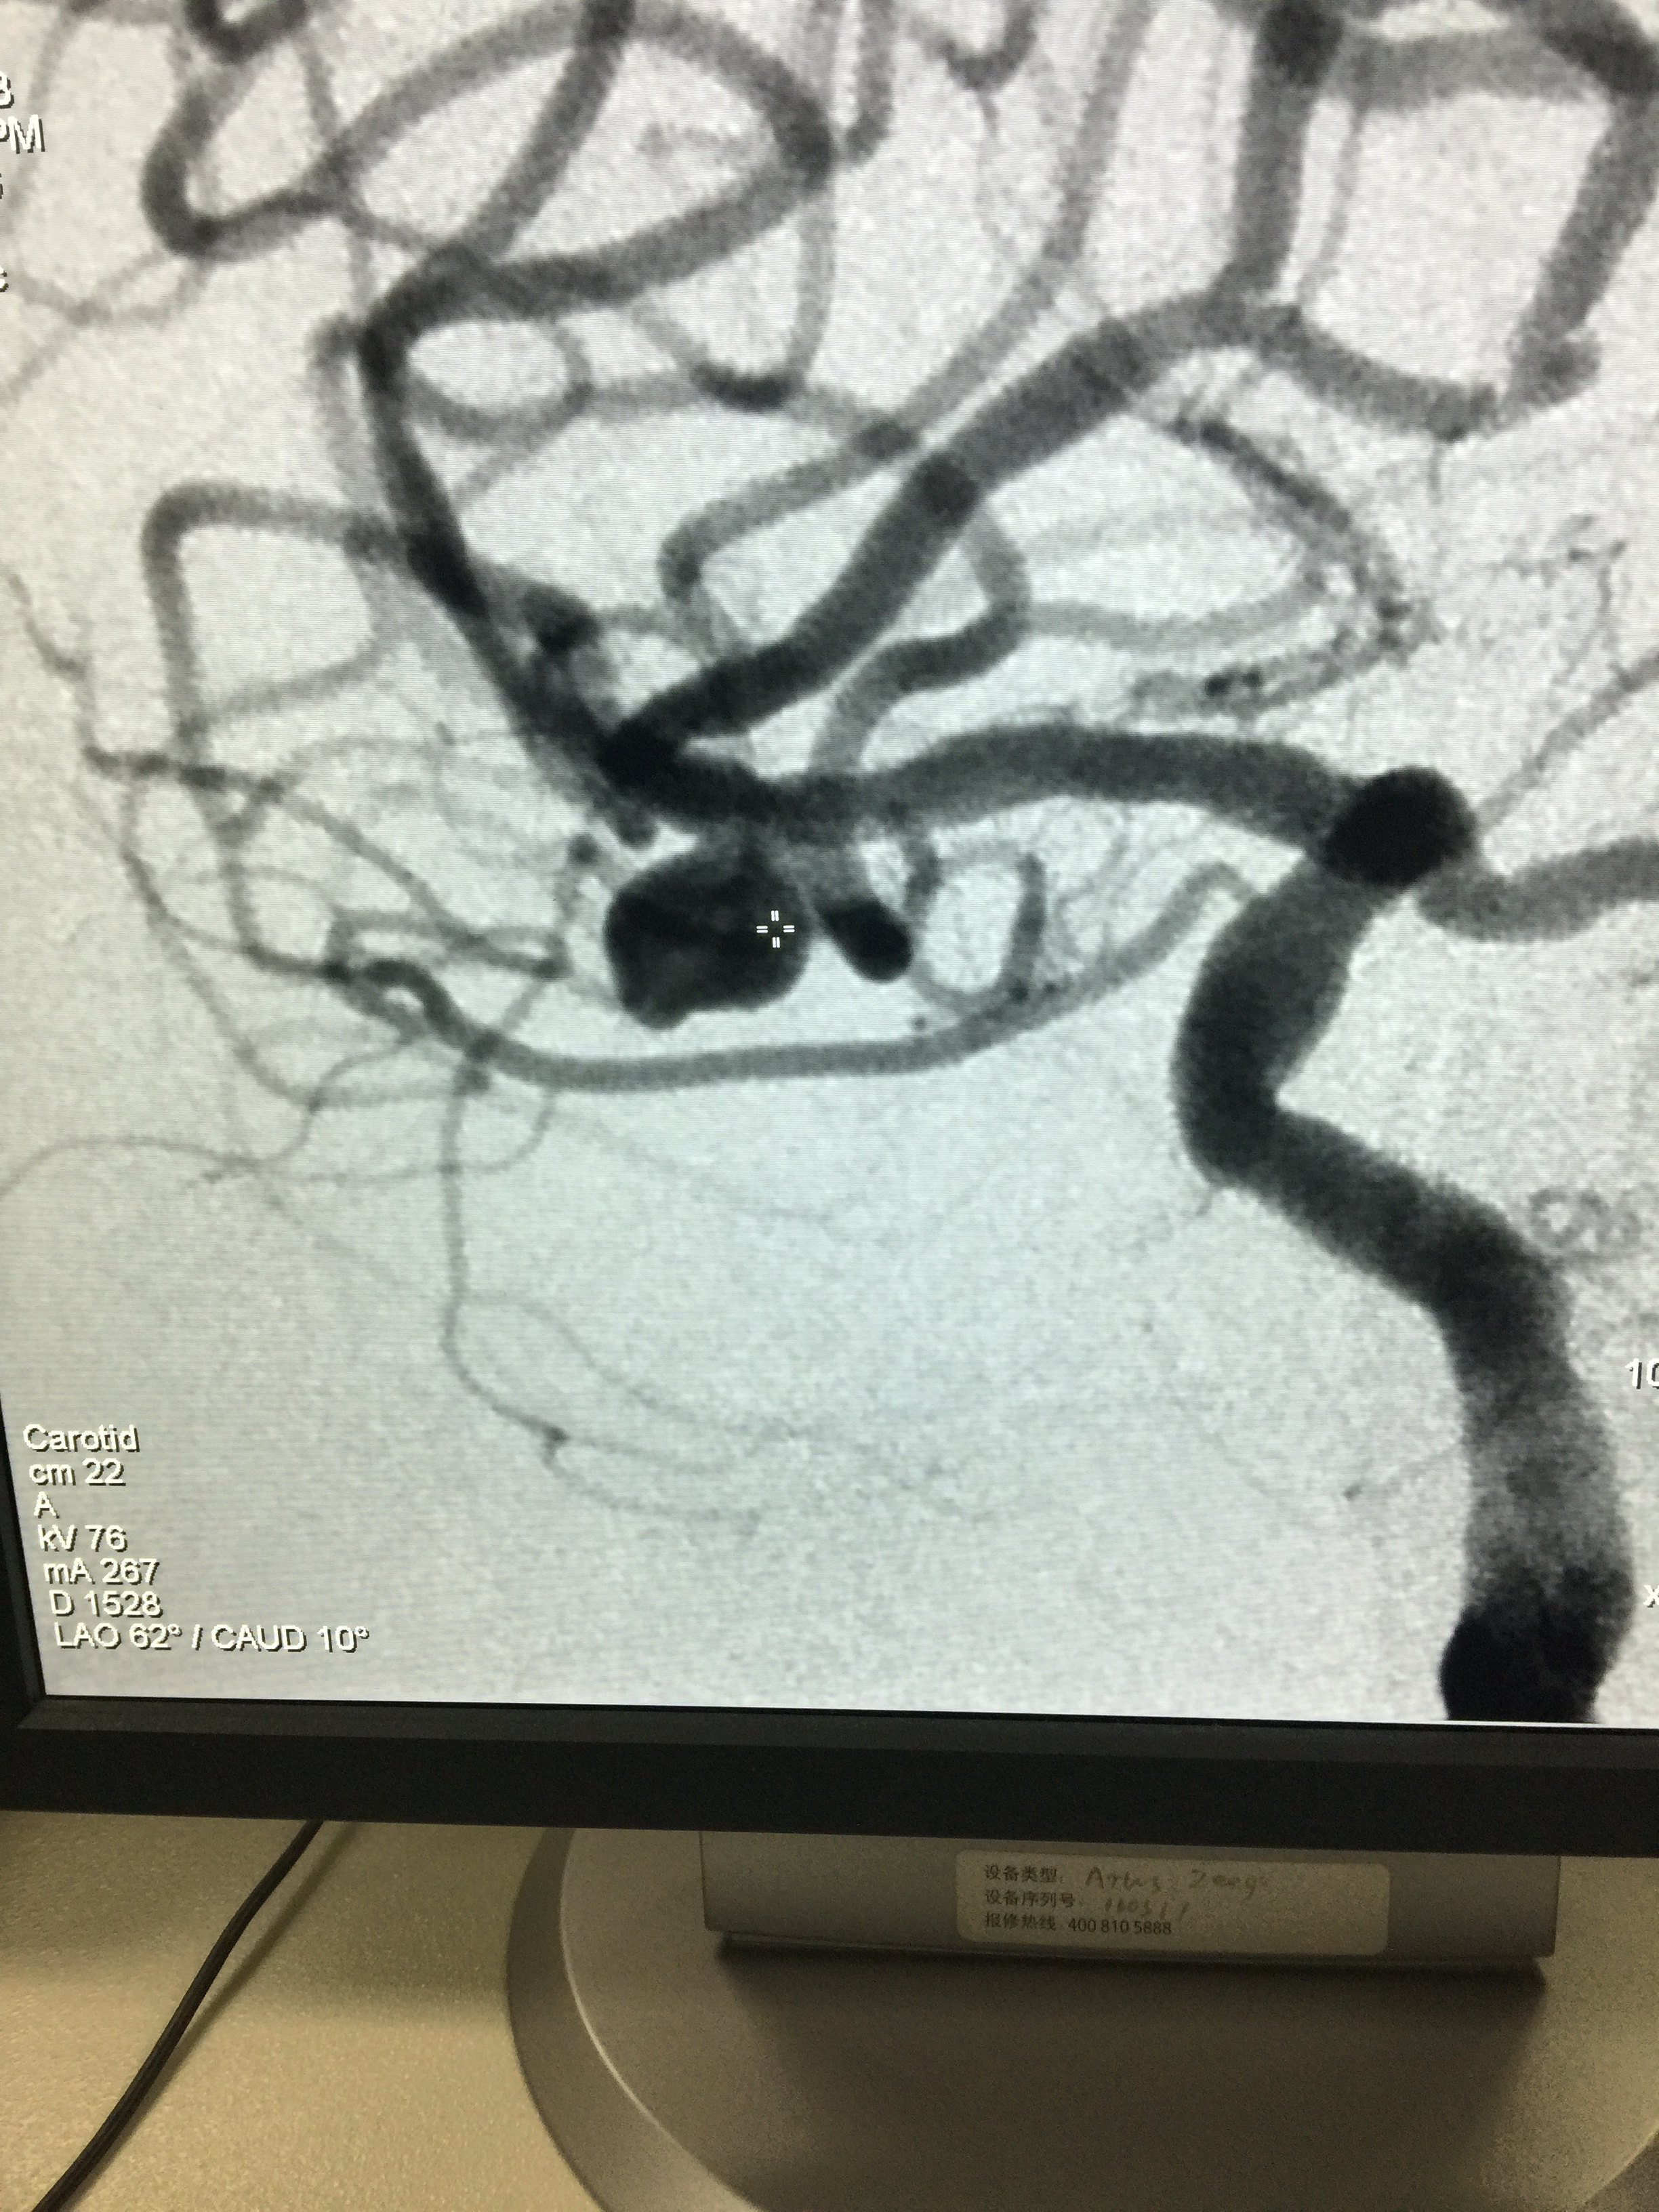

病例四:右侧大脑中分叉部动脉瘤

1534032349.png